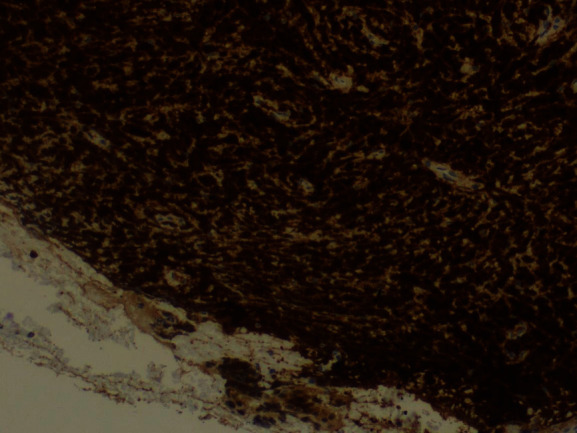

The tumor surface molecules were studied by immunophenotyping (Table 1) to clarify the nature of cancer and establish the appropriate treatment protocol. The positive Clusters of Differentiation (CD) were CDs 34, 45, 20, 79A, and 10 together with the marker MIB 1/Ki-67 (Figures 10–15).

Figure 10.

MIB 1/Ki-67: positive 100%.

3.3. Immunohistochemistry

Nowadays, proper diagnosis, classification of disease, and targeted therapeutic plans are based both on the classic morphologic features on microscopic biopsy examination and appropriate molecular adjuncts. Those adjuncts are appropriately selected immunophenotypic panels for tissue profiling and molecular genetics. It is important to mention, though, that there is no pathognomonic marker for a specific disease, and this explains that in each pathology study different immunophenotypic panels are selected [23].

In the case of assessing cervical biopsies, pathologists frequently use the marker Ki-67/MIB 1, as its expression represents “increased cell proliferation.” Furthermore, specifically at cervical pathological assessment, Ki-67 positivity is linked to poor prognosis in cervical cancer [24].

The neoplasm of the case presented exhibited immature characteristics; thus, CD34 and CD45 markers were used. At first, the tissue is stained CD34 positive in the case of hematopoietic disease when undifferentiated blasts are present (85–90% of B-ALL and B lymphoblastic lymphomas). Secondly, for CD45, a strong expression is seen in non-Hodgkin lymphomas; a weak expression is seen in acute leukemias (ALL, AML, and blastic natural killer cell neoplasms). In our case, the expression was positive, and this fact confirms the hematopoietic origin of the cervical tumor [23].